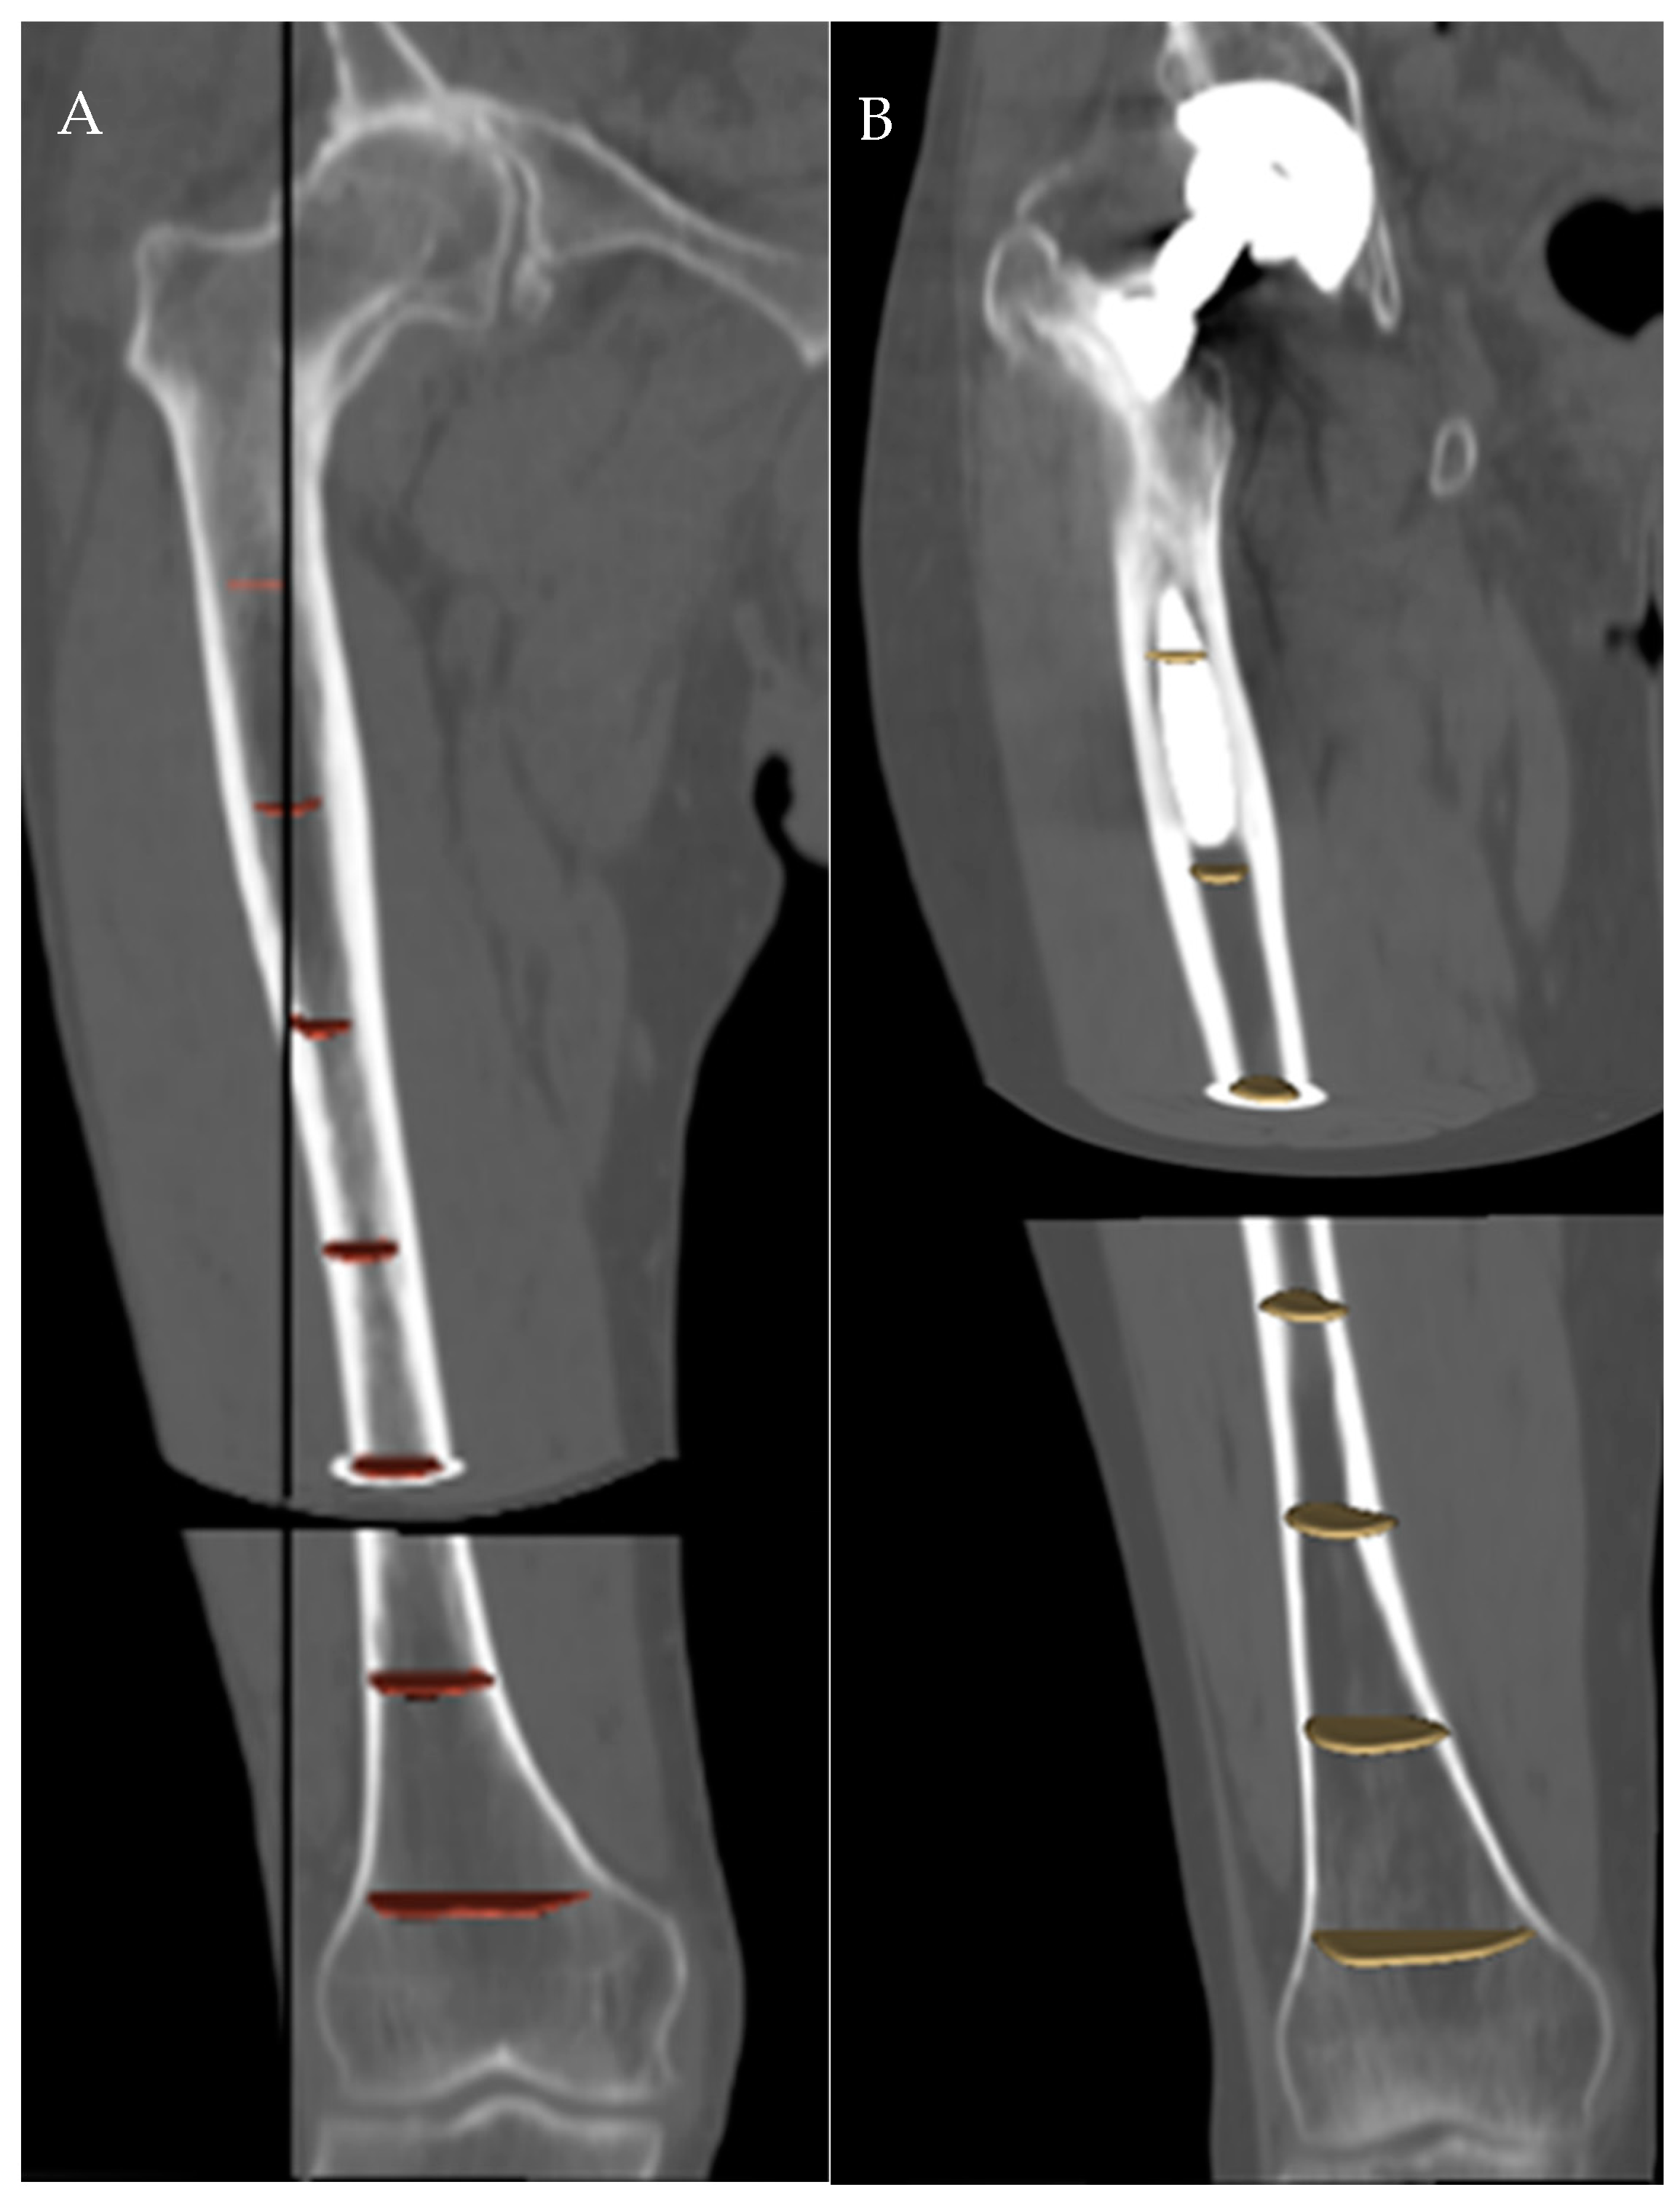

Figure 4. Comparison of the pre- and post-surgical femur curvatures in a prosthetic (A) and a native (B) side.

The difference in variations of the radius of curvature in the sagittal plane between the prosthetic and the control group was statistically significant for the proximal femoral segment (p = 0.004), but not for the mid-femoral segment (p = 0.56) (Table 4, Figure 4).

The case series showed a statistically significant rate of change in the proximal sagittal radius of curvature (p = 0.004) after at least 3 years from cementless THA compared to the contralateral untreated side used as a control. No differences could be observed in the middle segment. This finding demonstrated that a cementless stem increases the SFB in the sole proximal segment, and this change is substantially independent from the variations induced by the aging process (as shown by the untreated side).